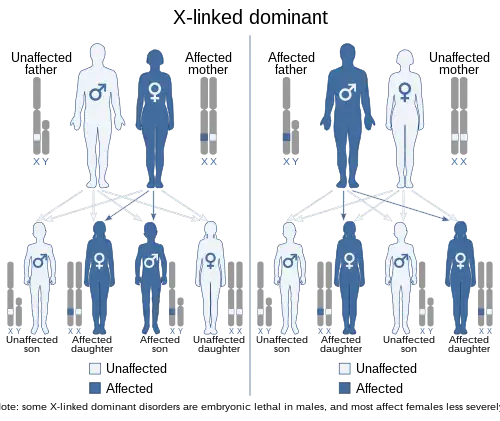

X-linked dominant traits do not necessarily affect males more than females (unlike X-linked recessive traits). The exact pattern of inheritance varies, depending on whether the father or the mother has the trait of interest. All fathers that are affected by an X-linked dominant disorder will have affected daughters but not affected sons. However, if the mother is also affected then sons will have a chance of being affected, depending on whether a dominant or recessive X chromosome is passed on. When the son is affected, the mother will always be affected. Some X-linked dominant conditions are embryonic lethal in males, making them appear to only occur in females.

In X-linked dominant inheritance, when the mother alone is the carrier of a mutated, or defective gene associated with a disease or disorder; she herself will have the disorder. Her children will inherit the disorder as follows:

- Of her daughters and sons: 50% will have the disorder, 50% will be completely unaffected. Children of either sex have an even chance of receiving either of their mother's two X chromosomes, one of which contains the defective gene in question.

When the father alone is the carrier of a defective gene associated with a disease or disorder, he too will have the disorder. His children will inherit the disorder as follows:

- Of his daughters: 100% will have the disorder, since all of his daughters will receive one copy of his single X chromosome.

- Of his sons: none will have the disorder; sons do not receive an X chromosome from their father.